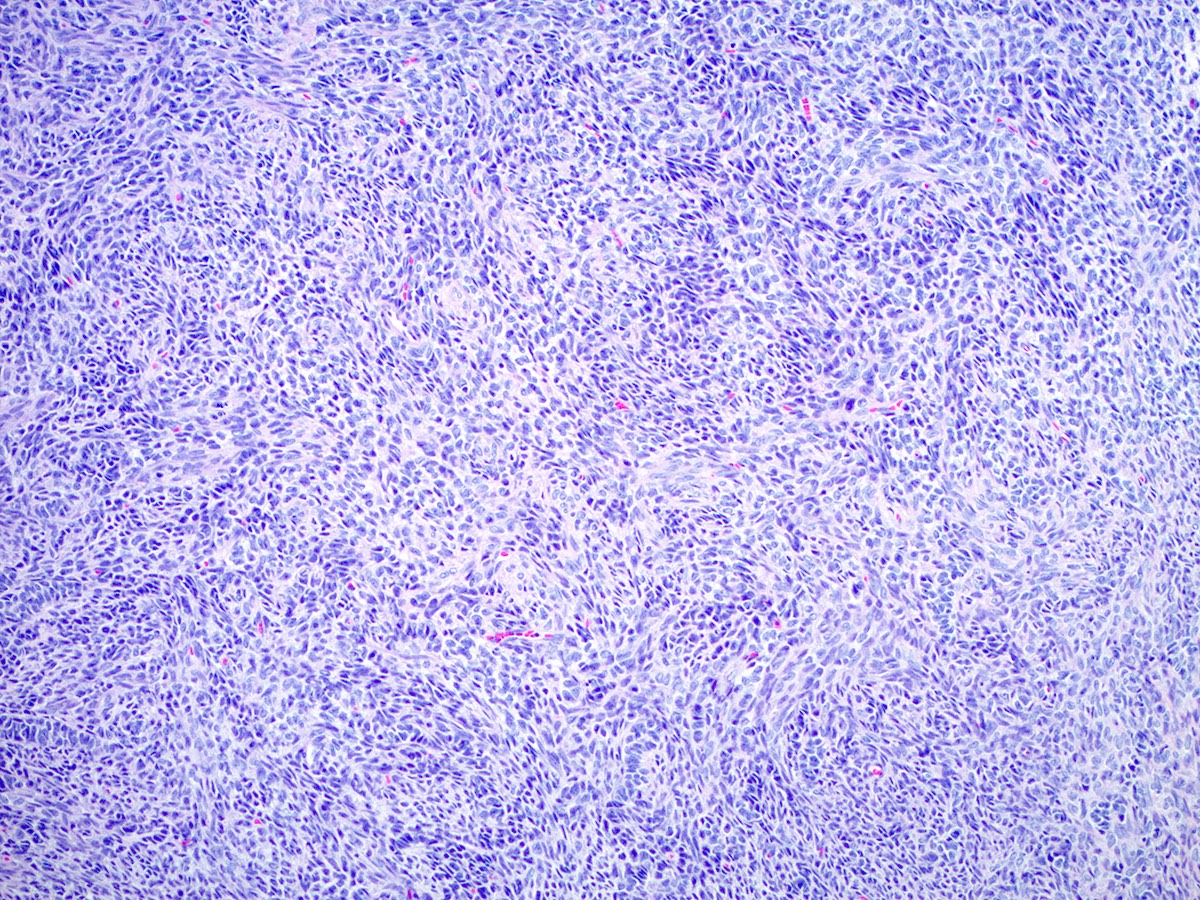

Microscopic (histologic) description

- Difficulty of histologic diagnosis increases with tumor grade

- Moderately differentiated

- Typically has a diffuse or lobulated architectural pattern and may show alternating hypo and hypercellularity on low magnification

- Sertoli cells form compressed tubules, cords or diffuse sheets and have hyperchromatic, oval or spindled nuclei with mild to moderate atypia and occasional mitotic figures (average 5 per 10 high power fields)

- Rare small clusters of Leydig cells are admixed with the Sertoli cell component

Microscopic (histologic) images